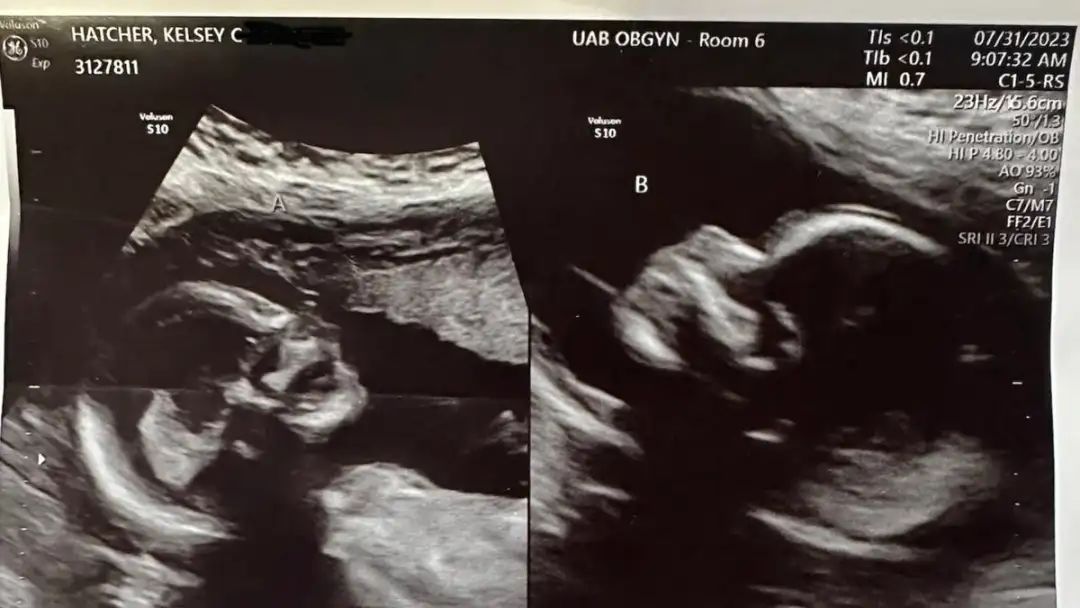

2023年7月31日的B超顯示,兩個胎兒發育正常。圖源/Fox News